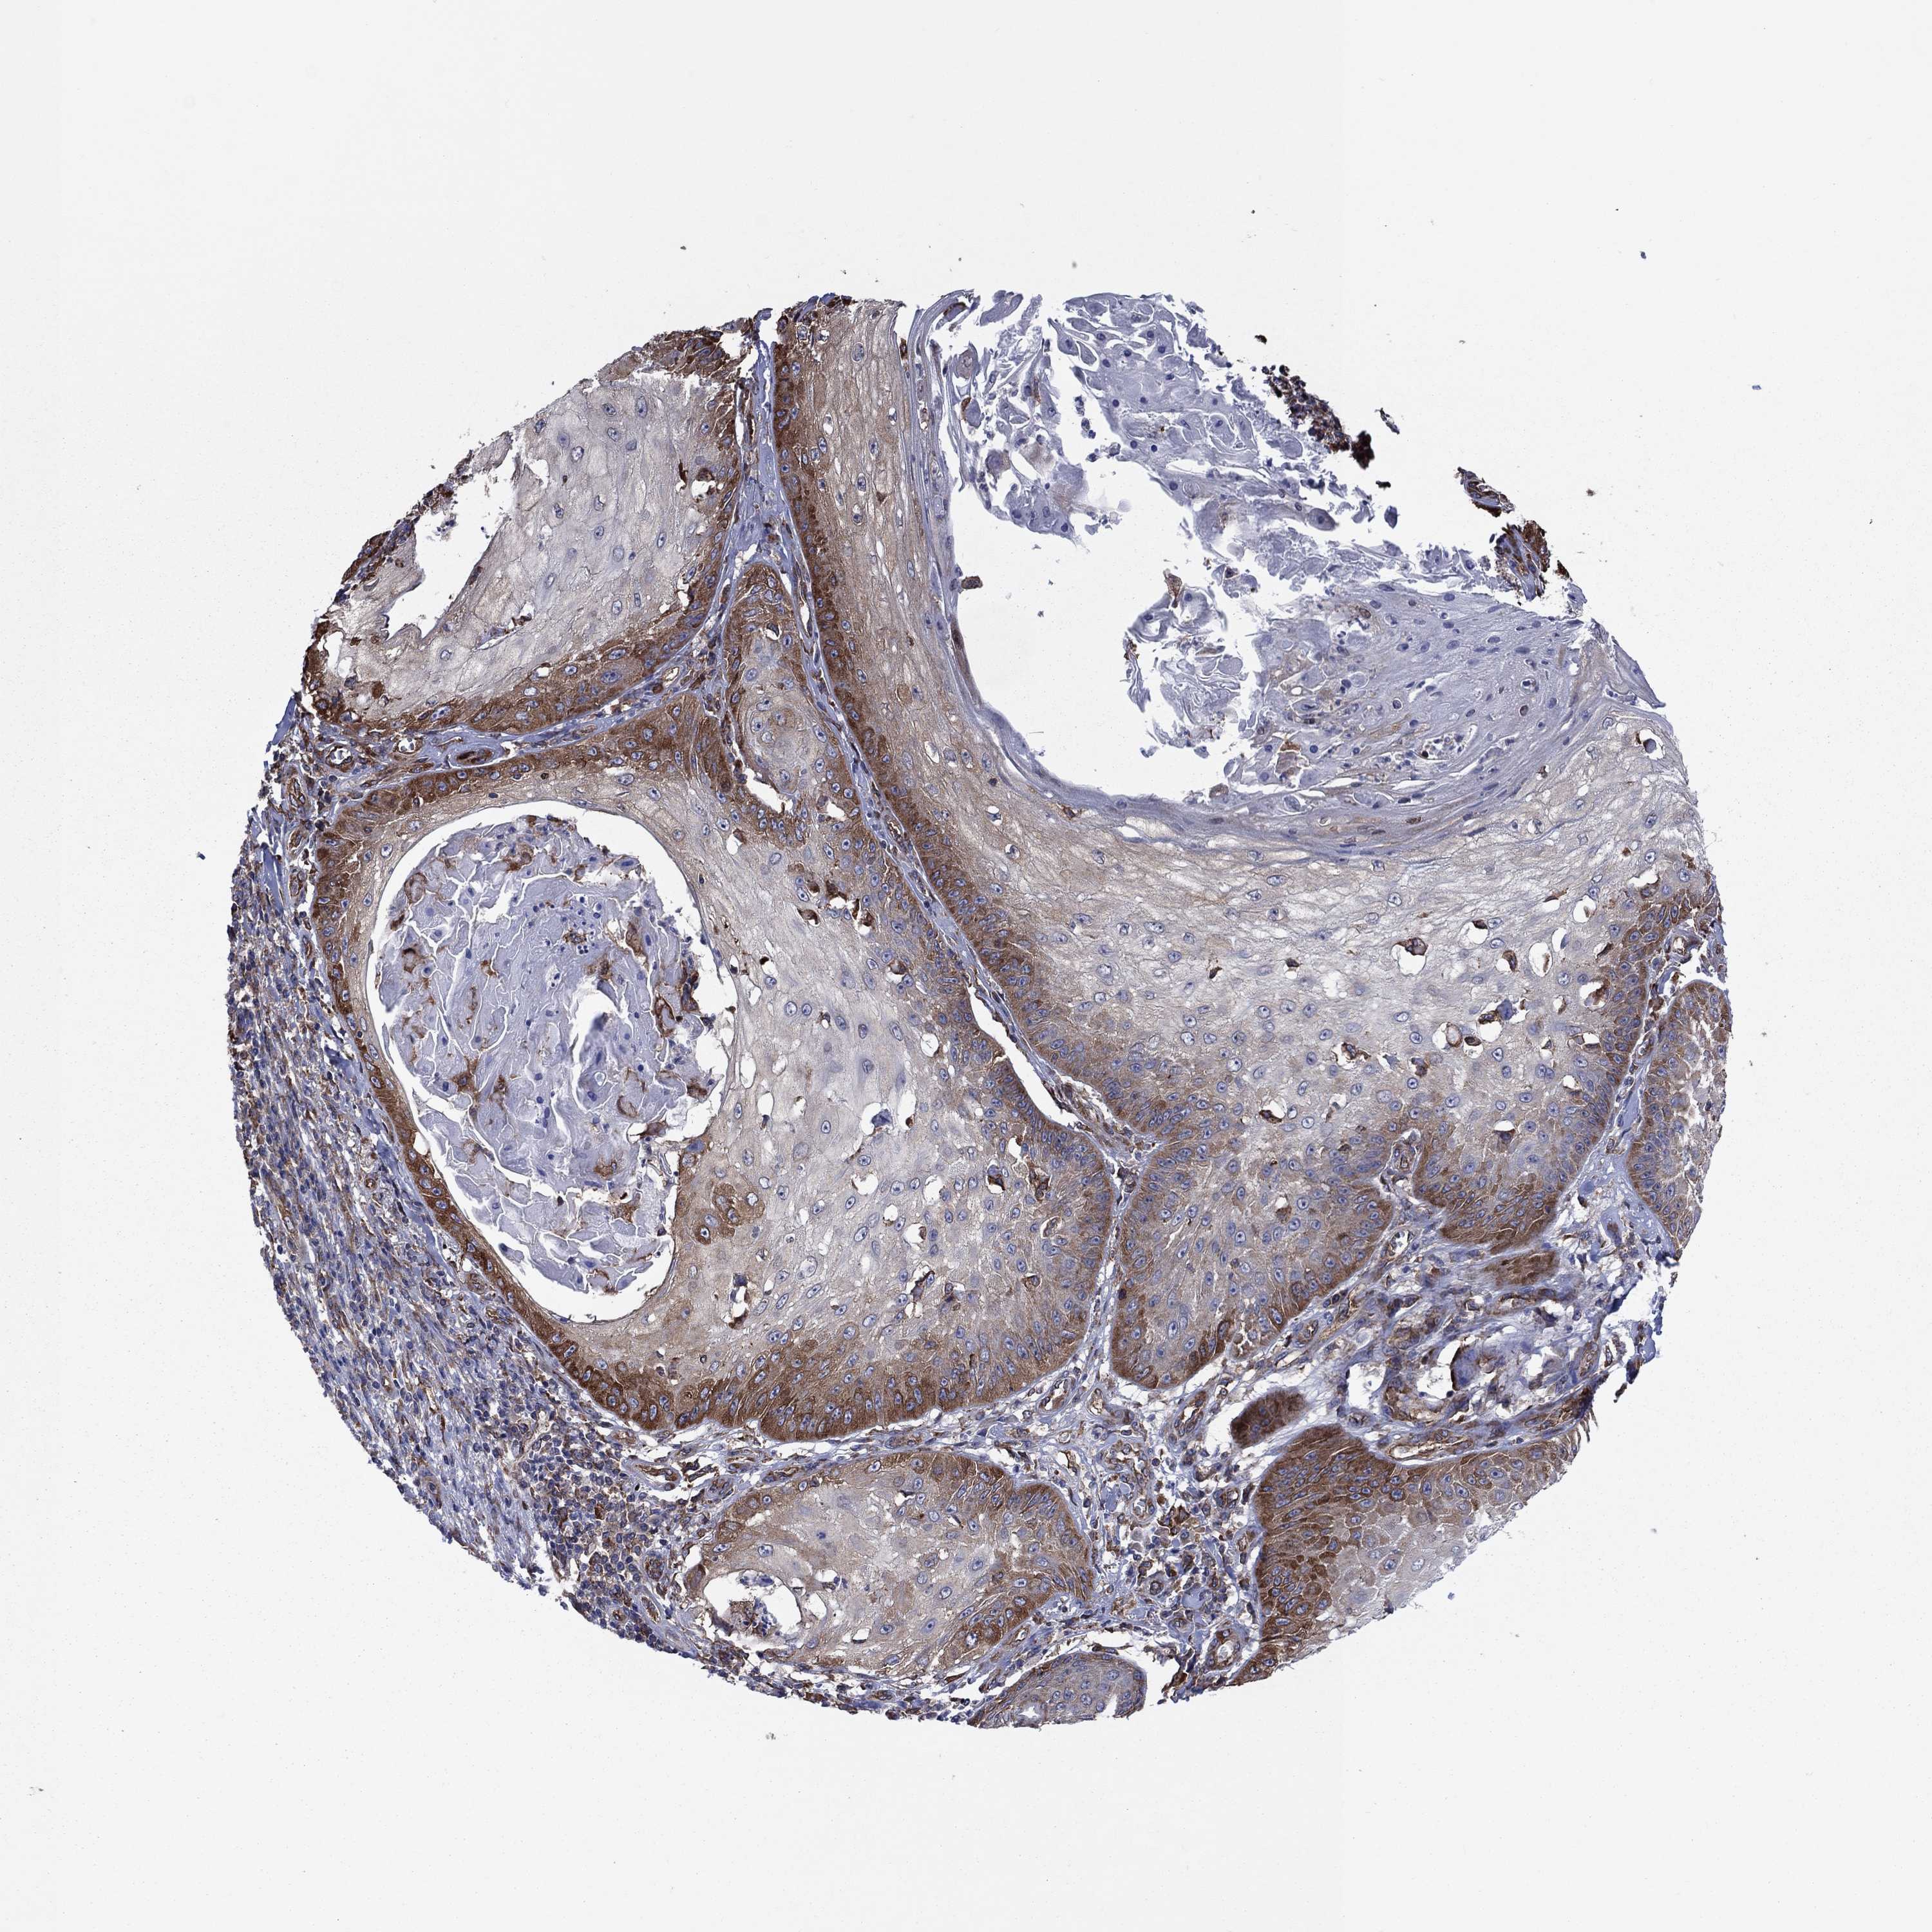

SKIN CANCER - Protein expressioni

A mouse-over function shows sample information and annotation data. Click on an image to view it in a full screen mode. Samples can be filtered based on level of antibody staining by selecting one or several of the following categories: high, medium, low and not detected. The assay and annotation is described here.

Antibody stainingi

Antibody staining in the annotated cell types in the current human tissue is reported as not detected, low, medium, or high, based on conventional immunohistochemistry profiling in selected tissues. This score is based on the combination of the staining intensity and fraction of stained cells.

Each image is clickable and will lead to virtual microscopy that enables deeper exploration of all samples and also displays staining intensity scores, fraction scores and subcellular localization as well as patient and tissue information for each sample.

Antibody CAB005875

Squamous cell carcinoma, metastatic, NOS

Squamous cell carcinoma, NOS